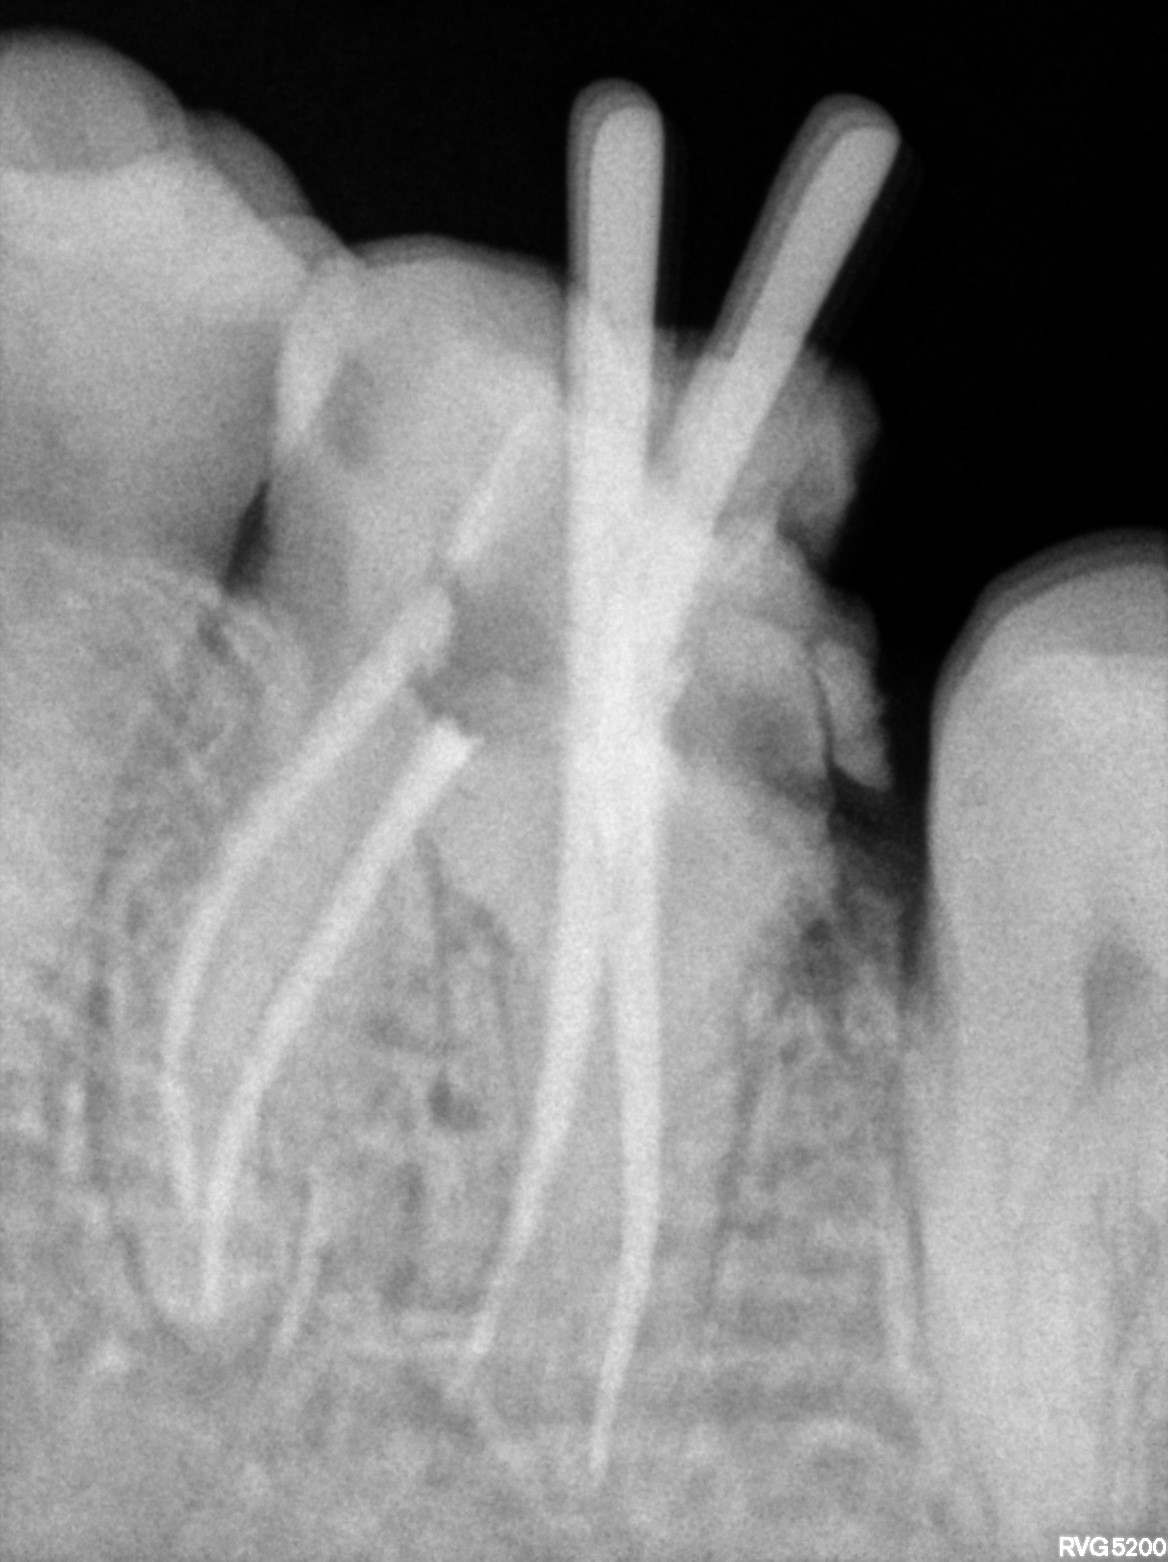

Dental Radiographs FHIR: DocumentReference · LOINC 24641-7

FHIR Bundle

xray_1772642539_0.jpg

24641-7

xray_1772642477_1.jpg

R55.jpg

xray_1770998647_1.jpg

R57.jpg

xray_1770476620_0.jpg

xray_1770998647_0.jpg

xray_1771259343_0.jpg

R56.jpg

xray_1772120353_0.jpg

R62.jpg

xray_1772642477_0.jpg